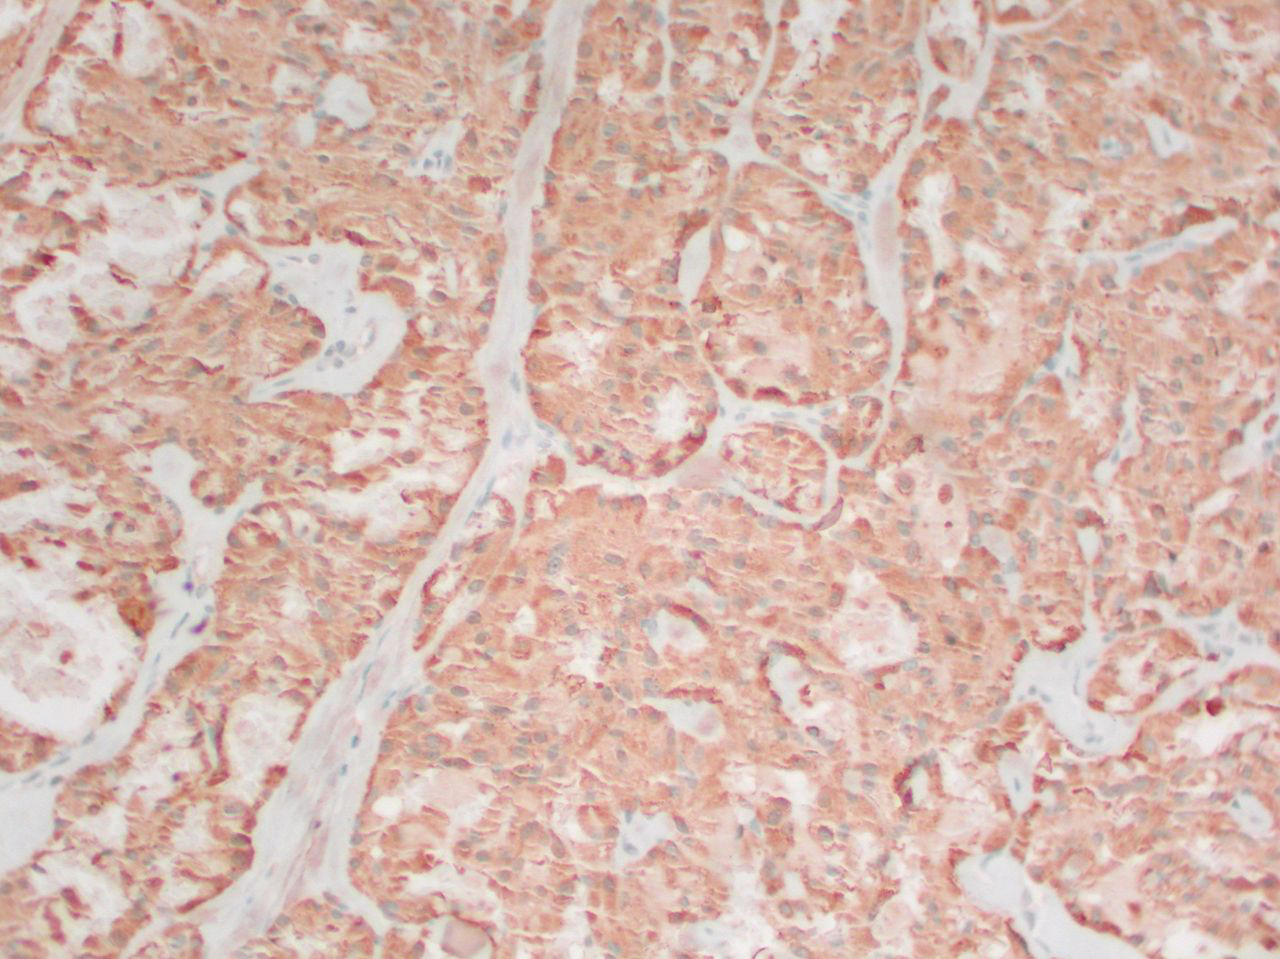

Medular: se origina en las células C parafoliculares del tiroides y representa aproximadamente del 1% al 3% de los cánceres de tiroides.[4] Se da de forma esporádica o puede ser hereditario. Una minoría (aproximadamente una cuarta parte) de los casos son hereditarios; por ejemplo, parte de los síndromes de neoplasia endocrina múltiple (NEM). Tiende a ser multicéntrico y a propagarse de manera temprana a los ganglios linfáticos.[Figure caption and citation for the preceding image starts]: Cáncer medular de tiroides: tinción H&E que muestra nidos de células tumoralesMohan V et al. BMJ Case Reports CP 2019;12:e230446; usado con autorización [Citation ends].

[Figure caption and citation for the preceding image starts]: Carcinoma medular tiroideo: tinción de calcitoninaMohan V et al. BMJ Case Reports CP 2019;12:e230446; usado con autorización [Citation ends].